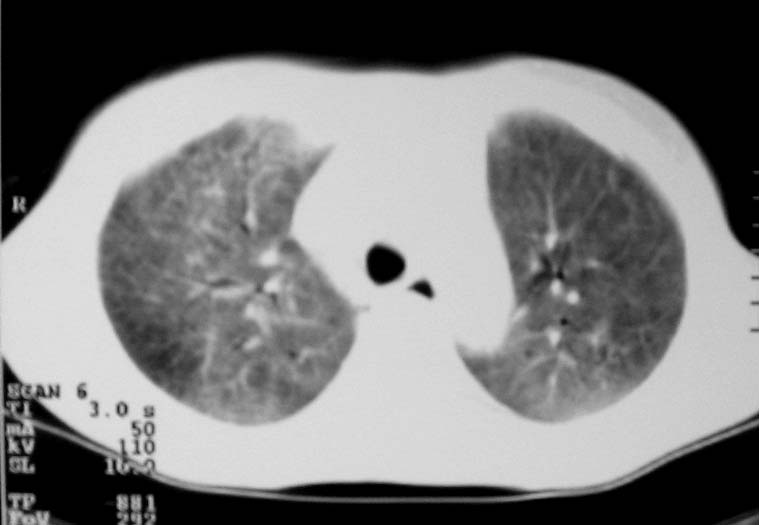

以下是引用zjzjr在2007-9-20 12:29:00的发言:[br]双肺磨玻璃改变,考虑肺水肿.

以下是引用yangzongshan在2007-9-20 18:29:00的发言:[br]两肺毛玻璃样改变,其内可见肺纹理影,无胸腔积液,故考虑肺泡蛋白沉积症

以下是引用276894491在2007-9-20 13:40:00的发言:[br]考虑肺水肿;外源性过敏性肺炎不排除。

以下是引用逸风在2007-9-20 20:45:00的发言:[br]两肺磨玻璃样改变,临床病史短,发热,考虑病毒感染合并右肺代偿性肺气肿.待排肺水肿,病史短,不支持肺泡蛋白沉着症.